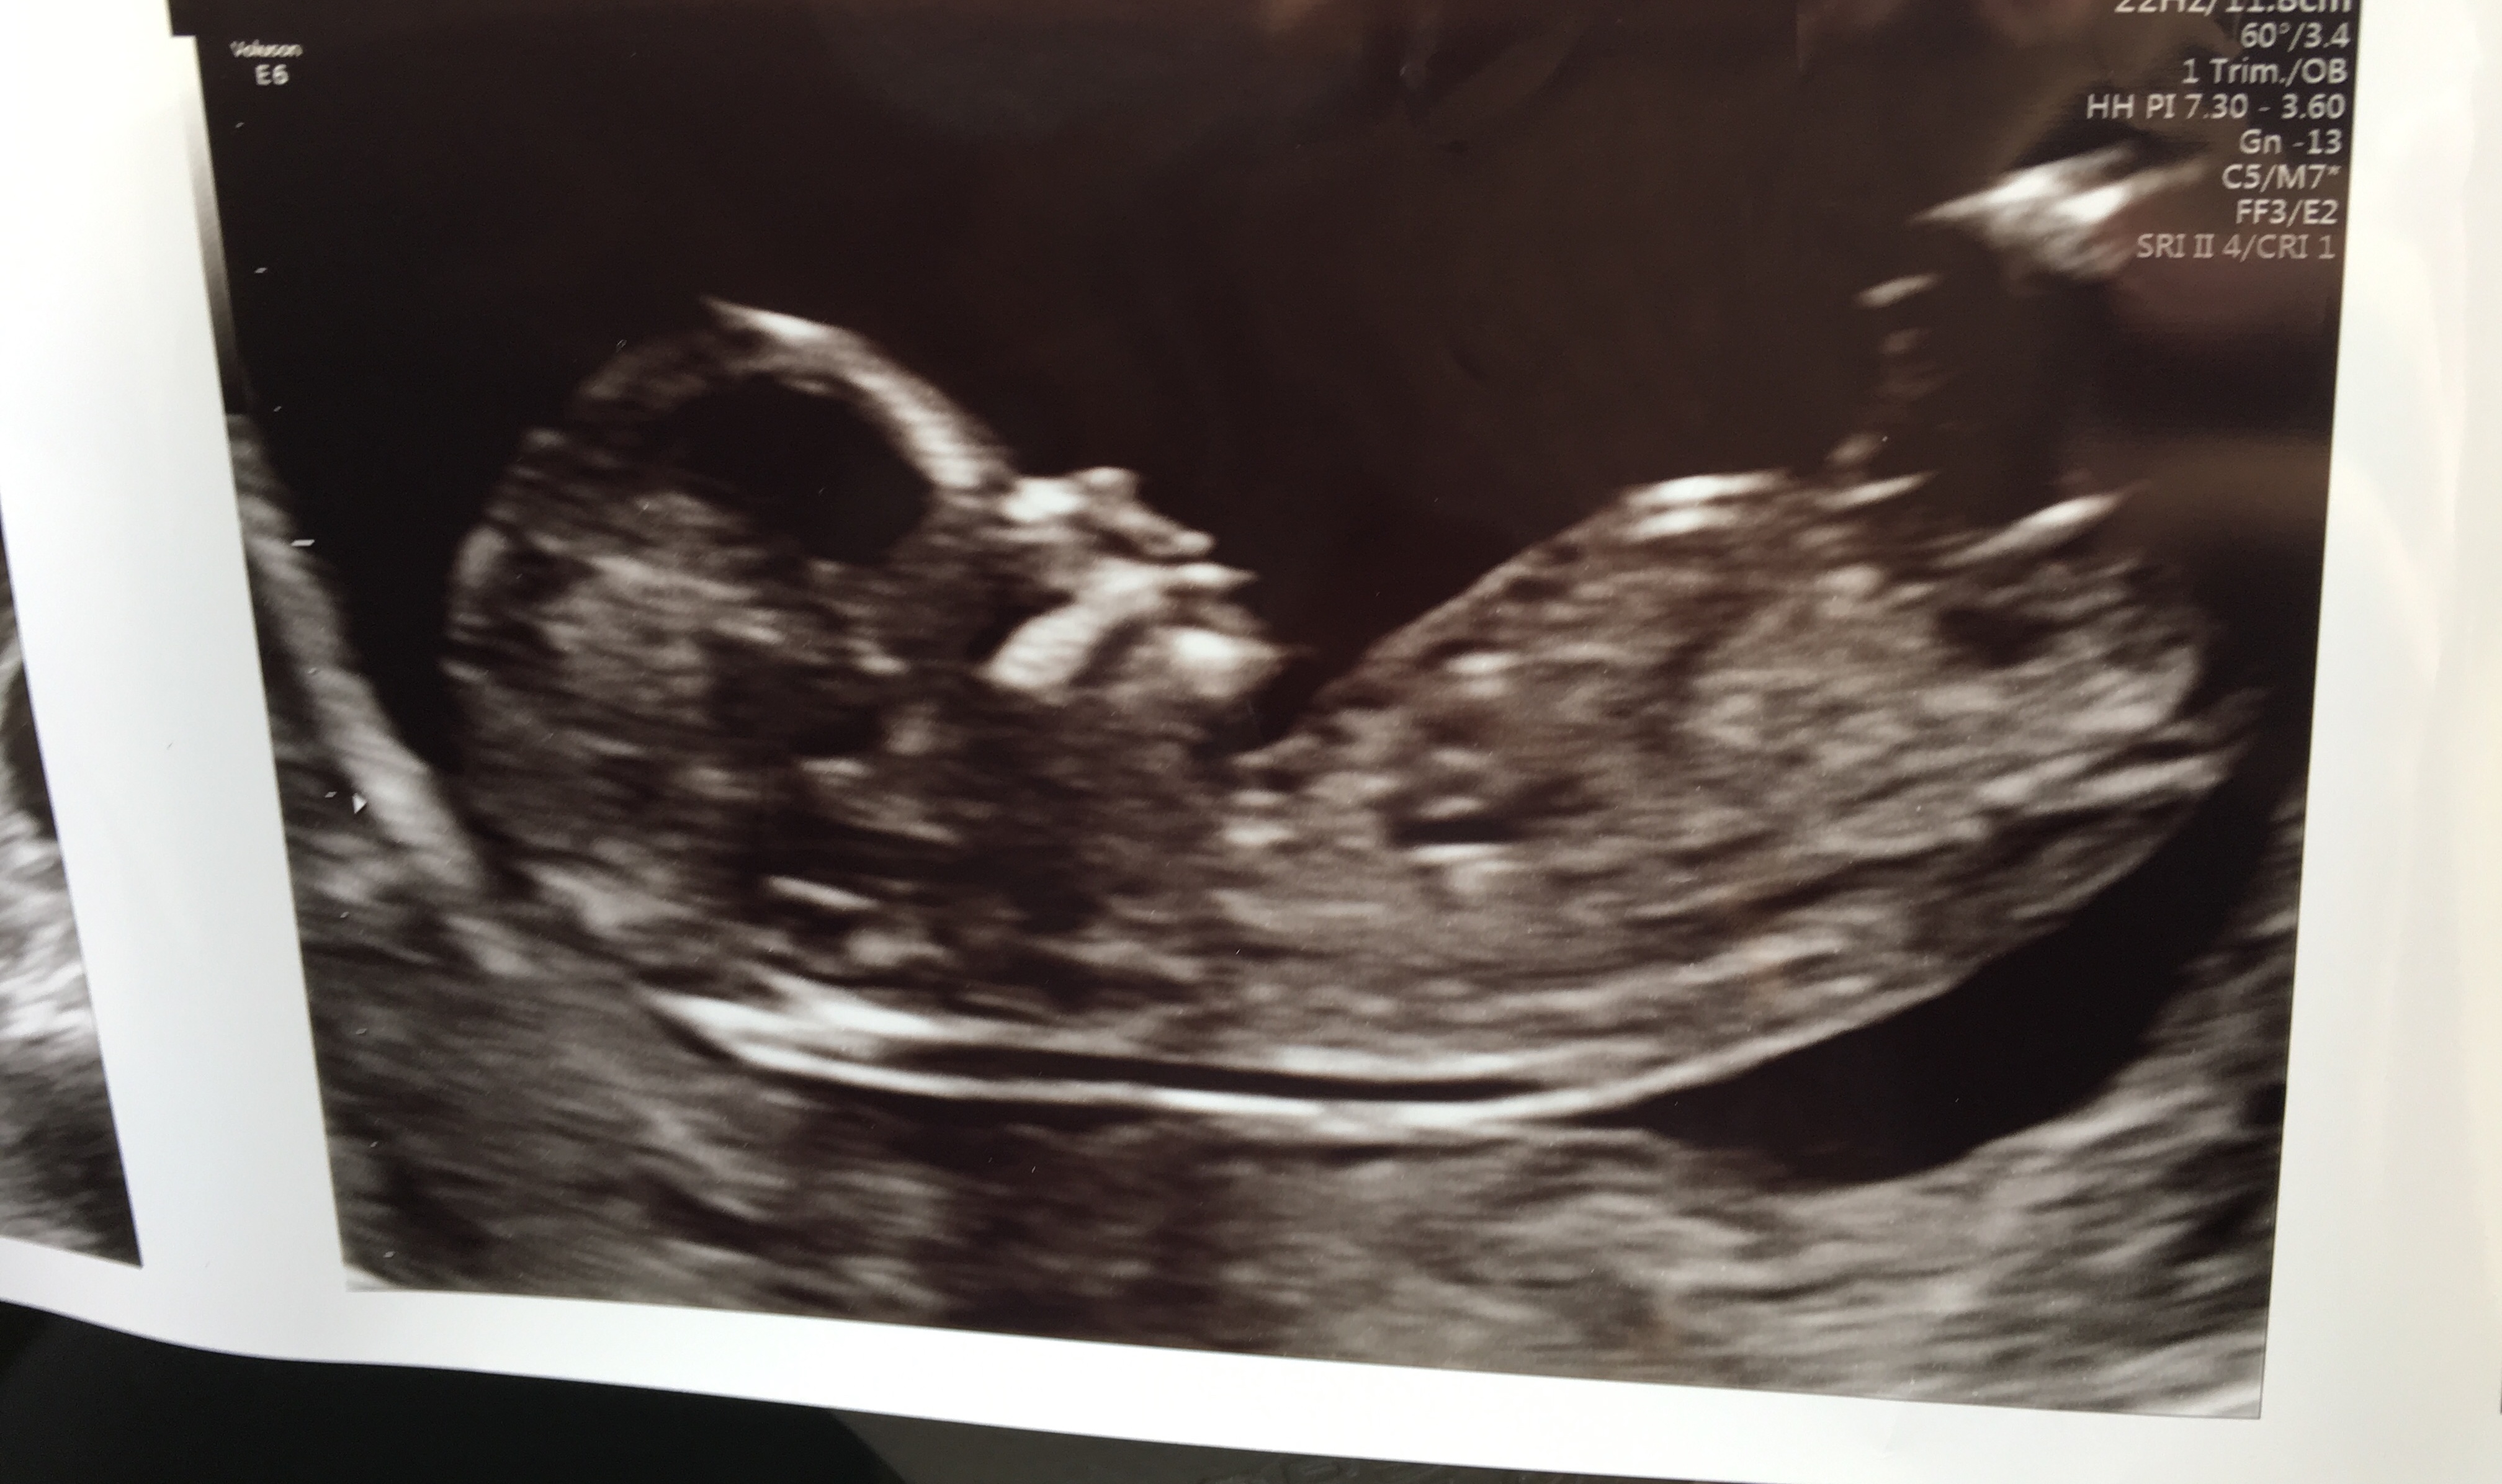

We are team green but I still would love nub guesses! We had our NIPT ultrasound today and I’m definitely curious what everyone else sees based on this. What do you think?Attachment 38361

Leaning slightly girl but the nub looks a bit cut off so hard to say.

I’ll post my other pictures too in case that helps it look more clear!

That is a really tricky one! In one picture I would have said girly

But on another one I can see some stacking on the nub so would indicate a boy

Looks like it's 50/50 still!!

tentative pink lean but earlier and less clear than I'd like